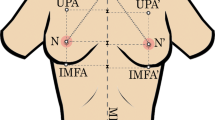

A prospective study was performed on 39 female-to-male transgender patients. Bilateral mastectomy was done for all patients. Preoperative anthropometric measurements were performed on 78 breasts of these patients. Weight of breasts was calculated postoperatively with digital scale (weight), and then volume of breasts was calculated with the calibrated container (water displacement technique). Authors built a model based on Python CatBoostClassifier. Finally, an android application was built for ease of real-time utilization.

Eight anthropometric measurements were collected preoperatively as independent variables. Breast vertical perimeter at lower half, upper pole, sternal notch to nipple and nipple to IMF had most correlation with volume and weight. Based on machine learning model, the following formula established: Breast volume = (breast width) × 24.69 + (nipple to IMF) × 49.03 − (sternal notch to nipple) × 1.34 + (anterior axillary line to medial border) × 6.57 − (upper pole) × 1.27 − (chest perimeter IMF) × 5.63 + (chest perimeter nipple) × 10.40 + (breast vertical perimeter at lower half) × 9.20 − 1133.74. The R2 of the model is 0.93, and RMSE is 62.4.